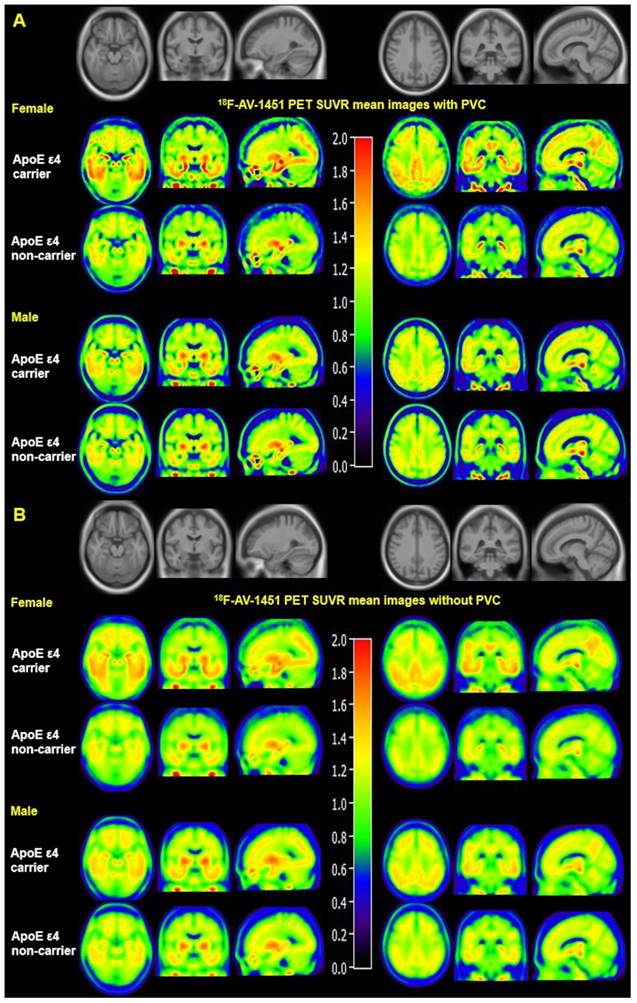

Mean SUVR images with and without PVC from MCI females and males are displayed in Figure 1. Figure 1A visually suggests that PVC increases 18F-AV-1451 SUVR contrast between ApoE ε4 carriers and non-carriers in the entorhinal cortex, amygdala, fusiform, parahippocampal gyrus, posterior cingulate, and occipital ROIs compared to non-PVC mean SUVR images (Figure 1B). Figure 1 also suggests that presence of the ApoE ε4 allele is associated with more tau deposition in women compared to men. Quantified SUVR from 18F-AV-1451 images with PVC in ROIs stratified by sex and ApoE status are displayed in Figure 2.

Mean 18F-AV-1451 PET SUVR images with and without partial volume correction in MCI individuals. Mean images were generated by computing the mean of images from ApoE ε4 carriers and non-carriers separately. Partial volume corrected images (A) show increased contrast and spatial resolution compared to non-PVC images (B). Both PVC and non-PVC images show an interaction effect between sex and ApoE ε4 status. Note that the mean images are averaged over all participants in each sex-ApoE ε4 group.